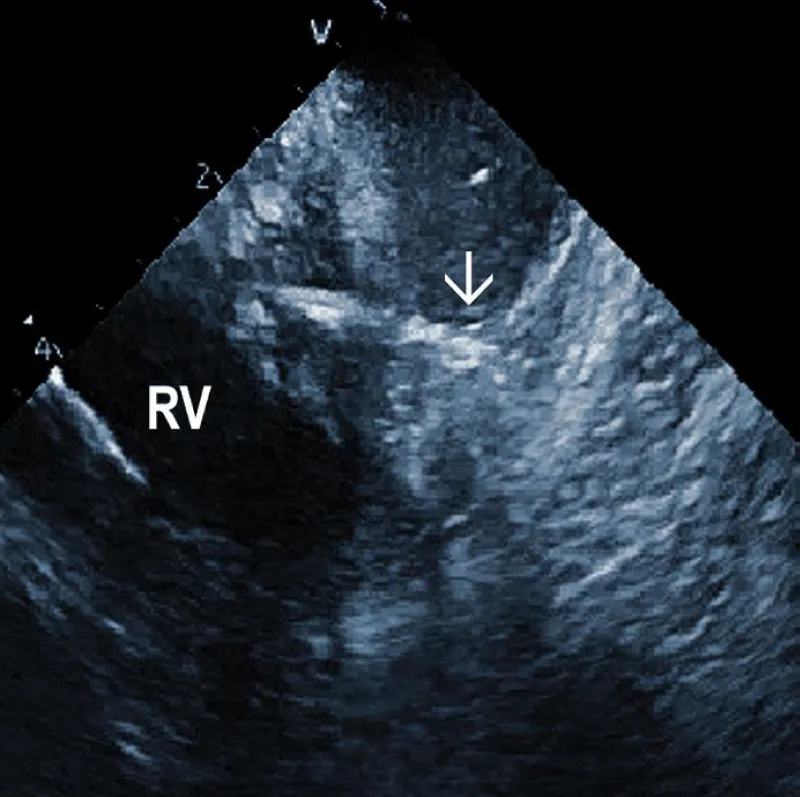

Residuals after TLE: Residual fibrotic tissue after TLE, called ghosts, has been described as a new phenomenon in cardiology (Figure 4). The presence of ghosts was first described by Rizzello, et al. using ICE [22]. Caiati, et al. studied a cohort of 40 patients using ICE before and after TLE to document the relationship between thrombotic or fibrotic reactions to the lead and with subsequent occurrence of ghosts [23]. ICE could identify thickened lead (thickness ≥ 1 mm than the vendor declared thickness in at least one lead) and fibrotic attachment to the cardiac wall in a substantial number of subjects. Thickening was noted in 25/40 patients (62%) overall, involving the atrial (2 patients (5%)) or the ventricular (9 patients (22.5%)) or both leads (14 patients (35%)). The fibrotic attachment was observed in 12/40 patients (30%). Both thickening and fibrotic attachments were significantly associated with subsequent ghosts (p < 0.001 and p = 0.002, respectively), but lead thickening had a higher prediction power. Narducci, et al. demonstrated that the presence of ghosts could be associated with a worse prognosis in device-related infective endocarditis [24]. Analyzing 217 TLE cases, the authors identified ghosts in 30 (14%) patients after TLE. In their study, endocarditis was one of the independent predictors of the presence of ghosts. Poterala, et al. detected ghosts after TLE in 19% of cases [25]. These residual fibrotic tissues were most often located along the originally implanted lead’s route. The local infection and infective endocarditis were associated with a larger number of ghosts after the removal procedure (p = 0.006). Besides frequent association with infection, detection of ghosts after TLE is also important for other reasons. Otherwise, they can be mistakenly interpreted in the echocardiographic examination as new pathological structures of unknown origin. In such a situation, the patient can be subject to unnecessary anticoagulant therapy, invasive diagnostic procedures, and/or cardiac surgery. Given the potential risks of ghosts, their presence should probably be noted on post-extraction imaging and might warrant closer post-extraction follow-up [4].

Figure 4: Ghosts within the superior vena cava (SVC) after removal of the ICD leads marked by arrows. AO: Aorta.